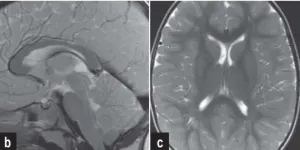

当获悉11岁女儿被诊断为脑干海绵状血管瘤时,湘湘内心充满坚定信念。无人能够预料,这颗深藏于脑干的海绵状血管瘤,竟会因出血压迫中脑导水管进而引发梗阻性脑积水。...